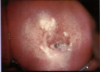

¿Clínicamente como se reconoce una cervicovaginitis aguda de una cervicovaginitis crónica?

- La cervicovaginitis aguda se caracteriza a la EF por espejo vaginal de un cérvix hiperémico y eritematoso, que es facilmente sangrante

- La cervicovaginitis crónica se caracteriza a la EF por espejo vaginal de un cérvix con los quistes de naboth (microtumoraciones benignas llenas de moco)